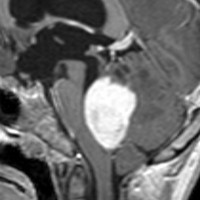

毛様細胞性星細胞腫 pilocytic astrocytoma

毛様細胞性星細胞腫です。左のガドリニウム増強T1像では髄芽腫と区別できませんが,真ん中のCISSの画像で低信号,右のT2強調画像で強い高信号になるのが特徴です。最上部に小さなのう胞が2つあります。